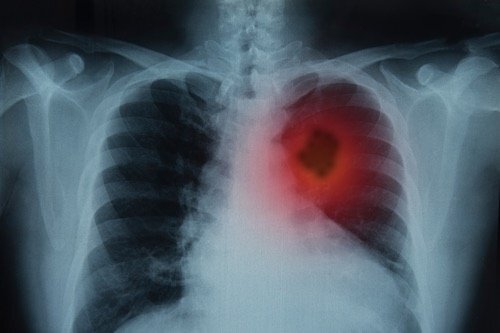

Диагностика рака легких

Сейчас для этого используют одновременное проведение компьютерной и позитронно-эмиссионной томографии, что позволяет видеть легкие, их анатомическую структуру и функциональные характеристики, а также очаги поражения в этом органе.

Чтобы упростить эту процедуру и сделать более дешевой, разработчики компаний Future Processing и NVIDIA, работая при сотрудничестве с экспертами в сфере расшифровки медицинских изображений, разработали программное обеспечение на базе алгоритмов искусственного интеллекта, позволяющее получать больше информации из КТ-сканов. Новое решение этих компаний, фокусирующееся на диагностике рака легких, позволяет медицинским специалистам при диагностике использовать только КТ-сканы, не применяя более дорогостоящую позитронно-эмиссионную томографию. Программа позволяет автоматически выделять раковые поражения в изображениях, существенно экономя время радиологов и врачей. Кроме этого, система позволяет измерять распространение опухоли по мере ее развития.

Новая технология не только упрощает процесс, но и позволяет снизить количество ошибочных диагнозов и сэкономить значительные средства.